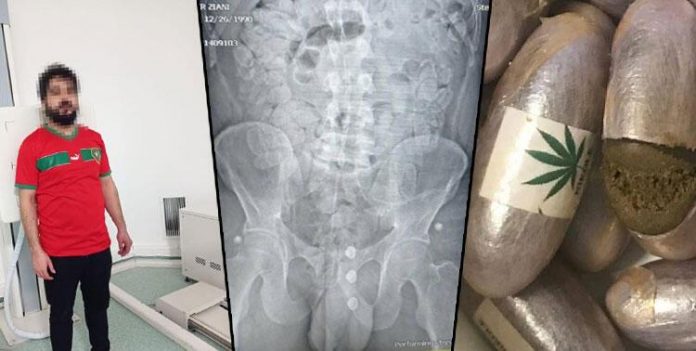

İl Emniyet Müdürlüğü Narkotik Suçlarla Mücadele Şube Müdürlüğü Narkotim ekipleri, 11 Aralık günü yaptıkları trafik uygulamasında, bir taksiyi şüphe üzerine durdurdu. Araçta yolcu olarak bulunan Fas uyruklu Zahr Zıani’nin tedirgin tavırlarından şüphelenen ekipler, kol ve koltuk altı bölgesinden gelen koku üzerine üst araması yaptı. Aramada, poşet içerisinde üzerinde kenevir yaprağı görseli olan kapsüller bulundu. 39 kapsül içerisindeki 339 gram maddenin reçine esrar olduğu belirlendi, Ziani gözaltına alındı.

İstanbul Sabiha Gökçen Havalimanı’ndan Türkiye’ye giriş yaptığı belirlenen şüphelinin, ülkesinden yutarak getirdiği uyuşturucu maddelerin bir kısmını doğal yollar ile çıkardığı ve poşete koyduğu saptandı.

Yalova Cumhuriyet Başsavcılığı’nın talimatıyla Yalova Devlet Hastanesi’ne götürülen şüphelinin tomografisinde mide ve bağırsaklarında çok sayıda kapsül olduğu tespit edildi. 3 gün boyunca hastanede gözlem altına tutulan şüphelinin mide ve sindirim sisteminde bulunan 155 kapsül içerisinde bin 191 gram reçine esrarın da doğal yollardan çıkartması sağlandı.

Emniyetten yapılan açıklamada, ele geçirilen toplam 194 kapsül içerisinde bin 545 gram reçine esrarın, il genelinde bu zaman kadar piyasa değeri açısından ele geçirilen en yüksek miktarda uyuşturucu olduğu belirtildi.